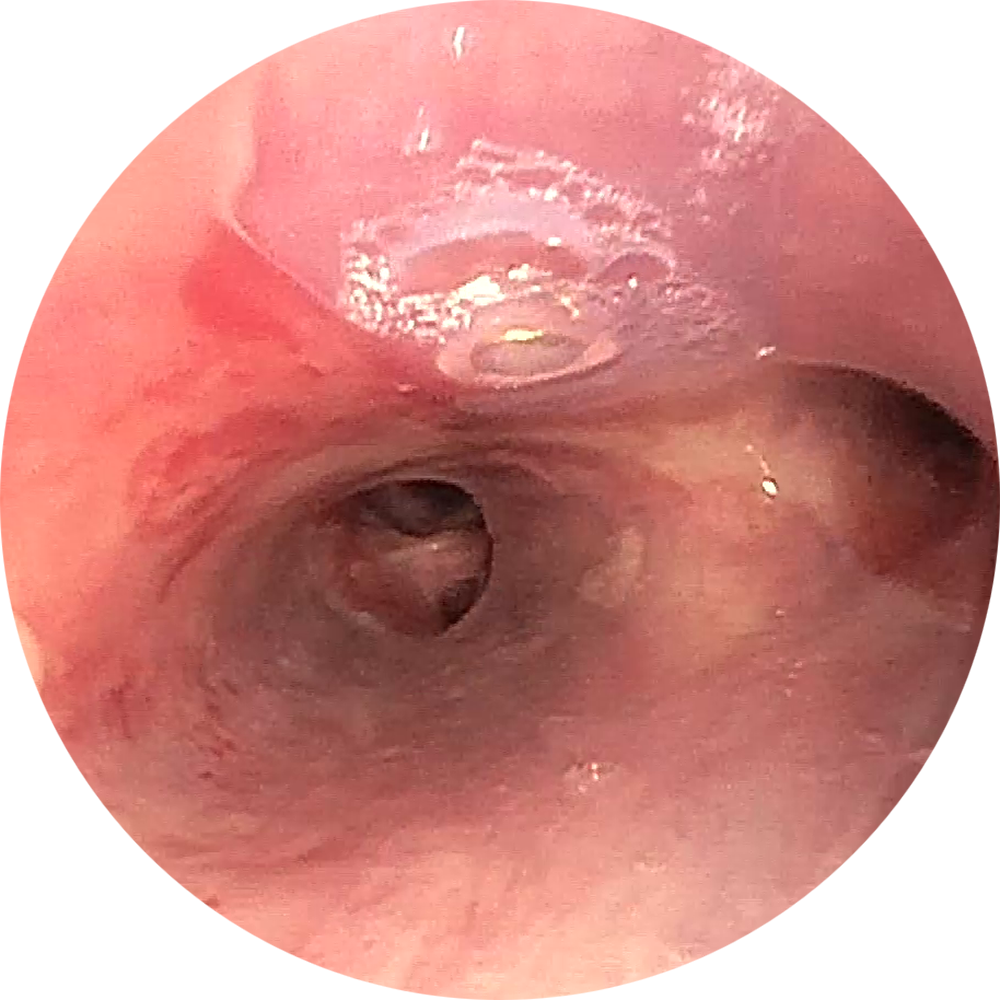

Erfolgreiche Implantation eines NOVATECH® 3D Stent bei einem Patienten mit Bronchomalazie im rechten Bronchus.

Bilder freundlicherweise zur Verfügung gestellt

von PD Dr. Daniel Franzen, Zürich.